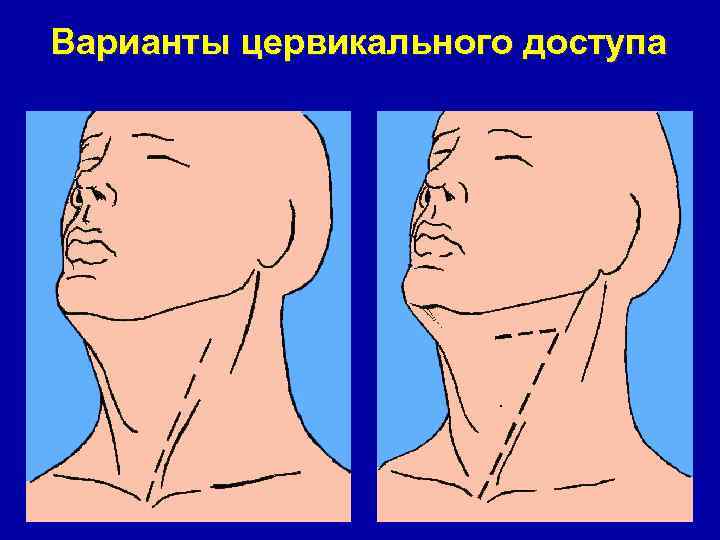

Варианты цервикального доступа